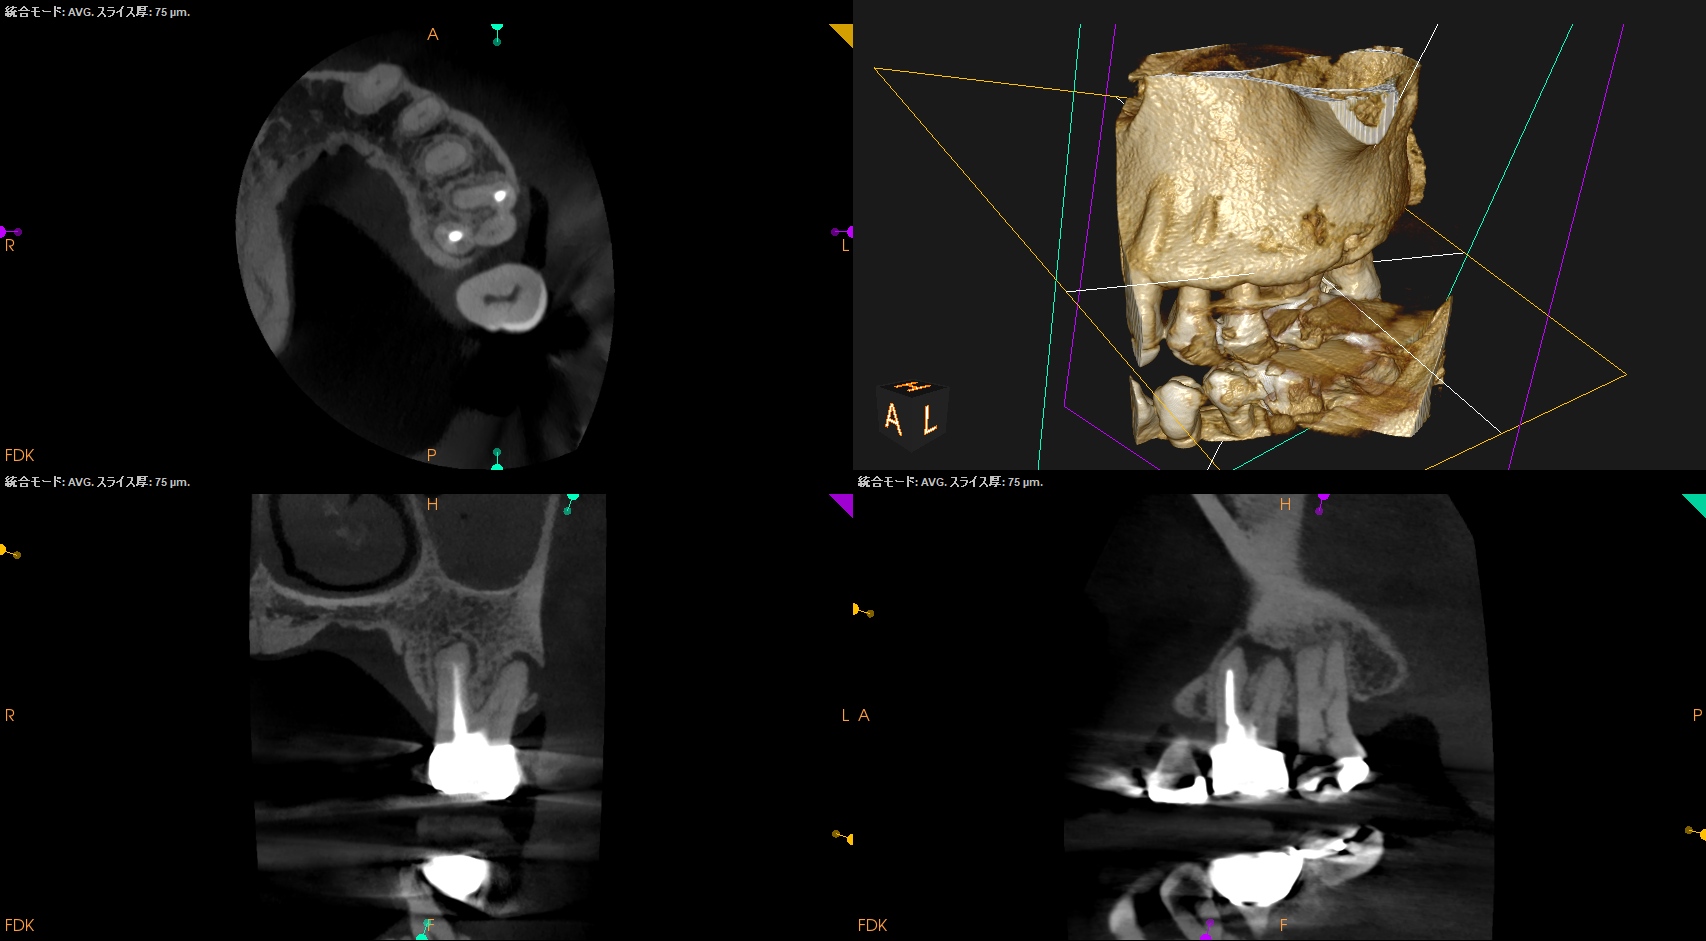

ということで治療時に以下のように修正した。

術後にPA, CBCTを撮影した。

問題はないだろう。

次回はMB,DBのApicoectomyである。